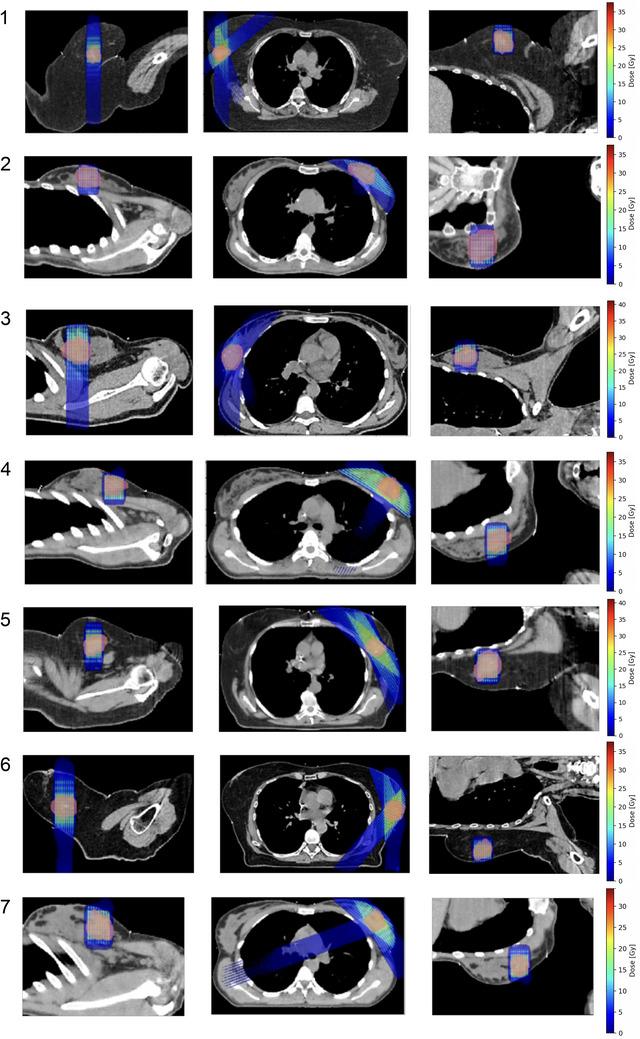

Seven unbiased breast cancer dosimetries of patients treated with stereotactic body radiotherapy (SBRT) (3 × 8 Gy, IMRT) were selected for the study. Photon mini-GRT was compared with SBRT using three main criteria: (i) the dose to organs at risk (OARs), (ii) the dose constraints dictated by normal tissue tolerance, and (iii) the lateral penumbra in OARs. Tumor coverage was evaluated in terms of normalized total dose at 8 Gy-fractions. The optimized SBRT by IMRT was realized at the Institut Curie, Paris, France. The dose in mini-GRT was calculated by means of Monte Carlo simulations based on the mini-GRT implementation realized at the University Hospital in Santiago de Compostela.

Compared to SBRT plans, mini-GRT resulted in a reduction of the mean dose to the lungs, heart, chest wall, and lymph nodes in the studied cases by a factor ranging from 50% to 100%. Additionally, valley, mean, and peak doses to normal tissues meet the dose tolerance limits for the considered OARs, the most challenging of all being the skin. The mean dose to the skin was reduced (20%-60% less) for most of the studied cases. Mini-GRT also yielded sharper lateral penumbras in the skin and lungs (size reduced by at least 50%). Similar tumor integral doses were obtained for the two treatment modalities.